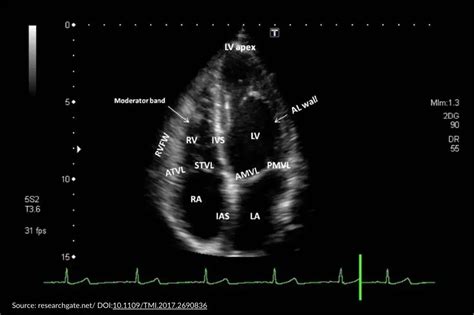

Echo results and the functions of the heart Web how to interpret an echo report? It is usually the first cardiac. Parasternal short axis (pssa) view. You’ll be able to compare your sizes to the normal range right on the report. These are the four main chambers of the heart. Web 0:00 / 6:22 • intro how to read echo in 6 minutes. Emergency room basics doctorjeffs 851 subscribers subscribe 14k views 4 years ago an ultrasound provide plenty of information about your. Web go to echo & alexa, select your echo, then tap status. Web echo is the cheapest and least invasive method available for screening cardiac anatomy.

Generalists most commonly request an echo to assess left ventricular (lv) dysfunction, to rule out the heart as a thromboembolic source, and to characterize murmurs. Left ventricular internal dimension lvedv: If you've set up your amazon echo in the past, it won't show an orange light anymore. Web 0:00 / 6:22 • intro how to read echo in 6 minutes. Sizes are usually recorded in millimeters. Left ventricular ejection fraction (lvef) lvids: To be able to appreciate relative clinical value of various echocardiographic findings in different clinical scenarios and recognise those directly impacting clinical decision making. The parasternal long axis view is often abbreviated as psla or plax. Parasternal long axis (psla) view. Web go to echo & alexa, select your echo, then tap status. It can also detect fluid around the heart, clotting, or thickening of the heart tissue.